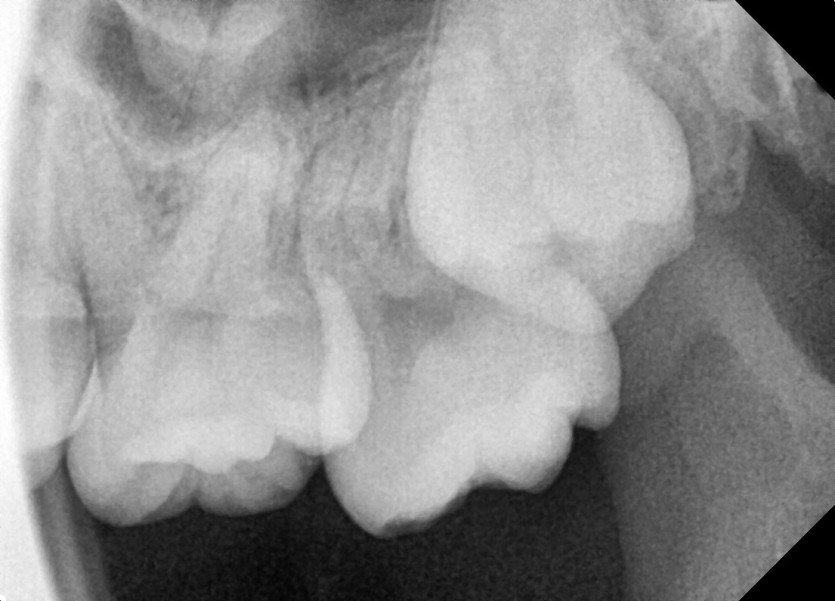

#28,38 사랑니 발치

구강외과 전문의가 당일 발치했습니다.